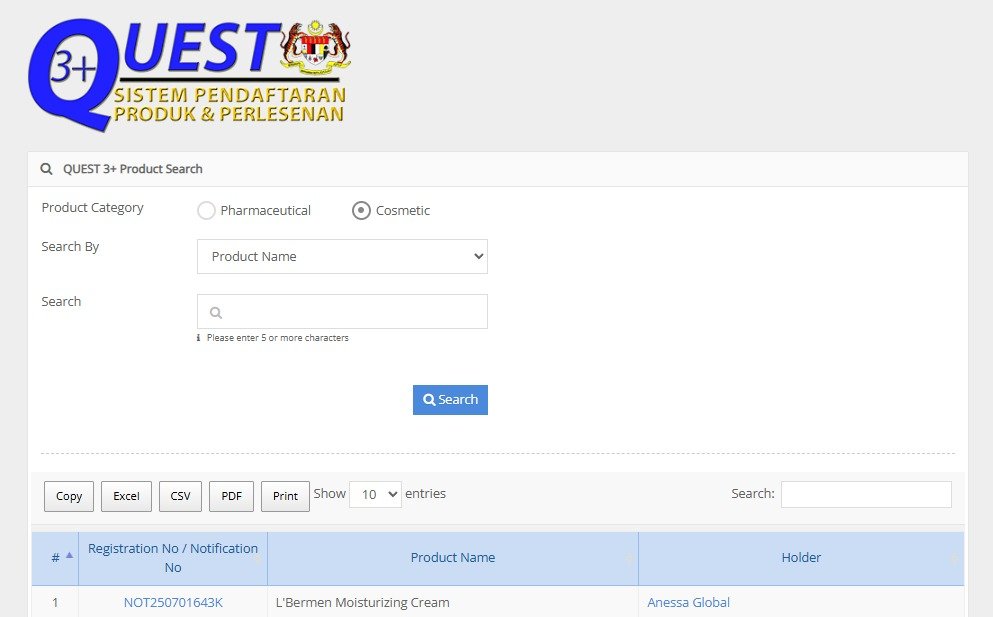

Krim yang Telah Disahkan TIADA Bahan Terlarang (Non-Toxic) & Lulus KKM

Tonton Video Penerangan Dr Pakar Sakit Tuan